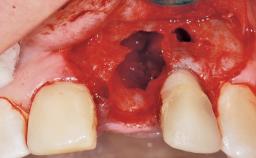

Late Placement of an Implant in a Maxillary Left Central Incisor Site

A 30-year-old female patient had lost tooth 21 and was referred to our clinic for consultation and treatment. Due to advanced apical infection, tooth 21 had been extracted two months earlier at another clinic and an acrylic-resin tooth had been bonded to the adjacent teeth. The patient desired implant treatment to avoid any damage to the adjacent natural teeth. While the patient had no history of any systemic disorder, she was a heavy smoker and exhibited medium to advanced periodontitis in the entire jaw. After the initial treatment to achieve a pocket probing depth of less than 4 mm and no bleeding on probing, a decrease in the height of the papillae mesial and distal to the extraction site and overall gingival recession were observed.

Bone Augmentation Horizontal|Staged

Augmentation Materials Autogenous chips|Membrane

Soft Tissue Anatomy Intact Defective

Bone Volume Horizontally and vertically sufficient Horizontally deficient Deficient vertically or deficient vertically AND horizontally

Bone Volume Deficient horizontally, requiring prior grafting